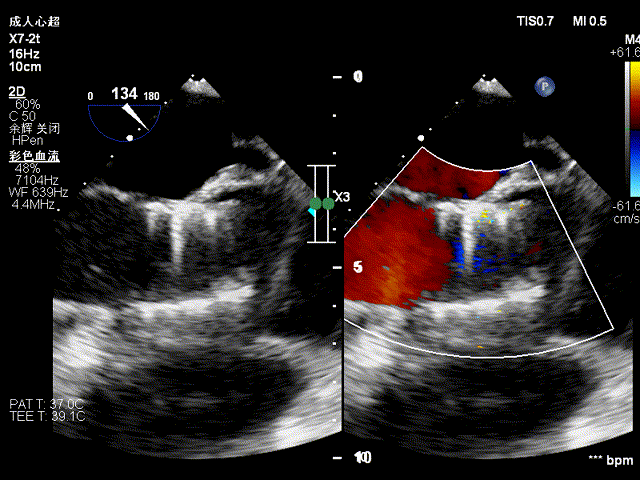

术前食道超声提示二尖瓣生物瓣大量反流:

即刻行食道超声显示无瓣周漏:

三维食道超声显示瓣架展开呈圆形,形态满意: